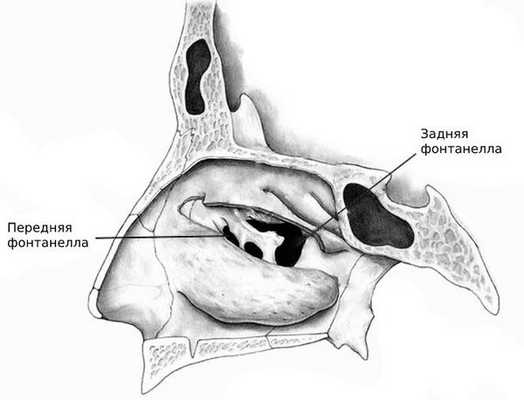

Эндоскопия

Врач осматривает полость носа жёстким или гибким эндоскопом. Метод позволяет оценить состояние выводного соустья, а также наличие или отсутствие отделяемого из синусов. Визуализировать кисту можно, если есть фонтанелла — добавочное соустье или дополнительное отверстие на стенке верхнечелюстной пазухи [9] .